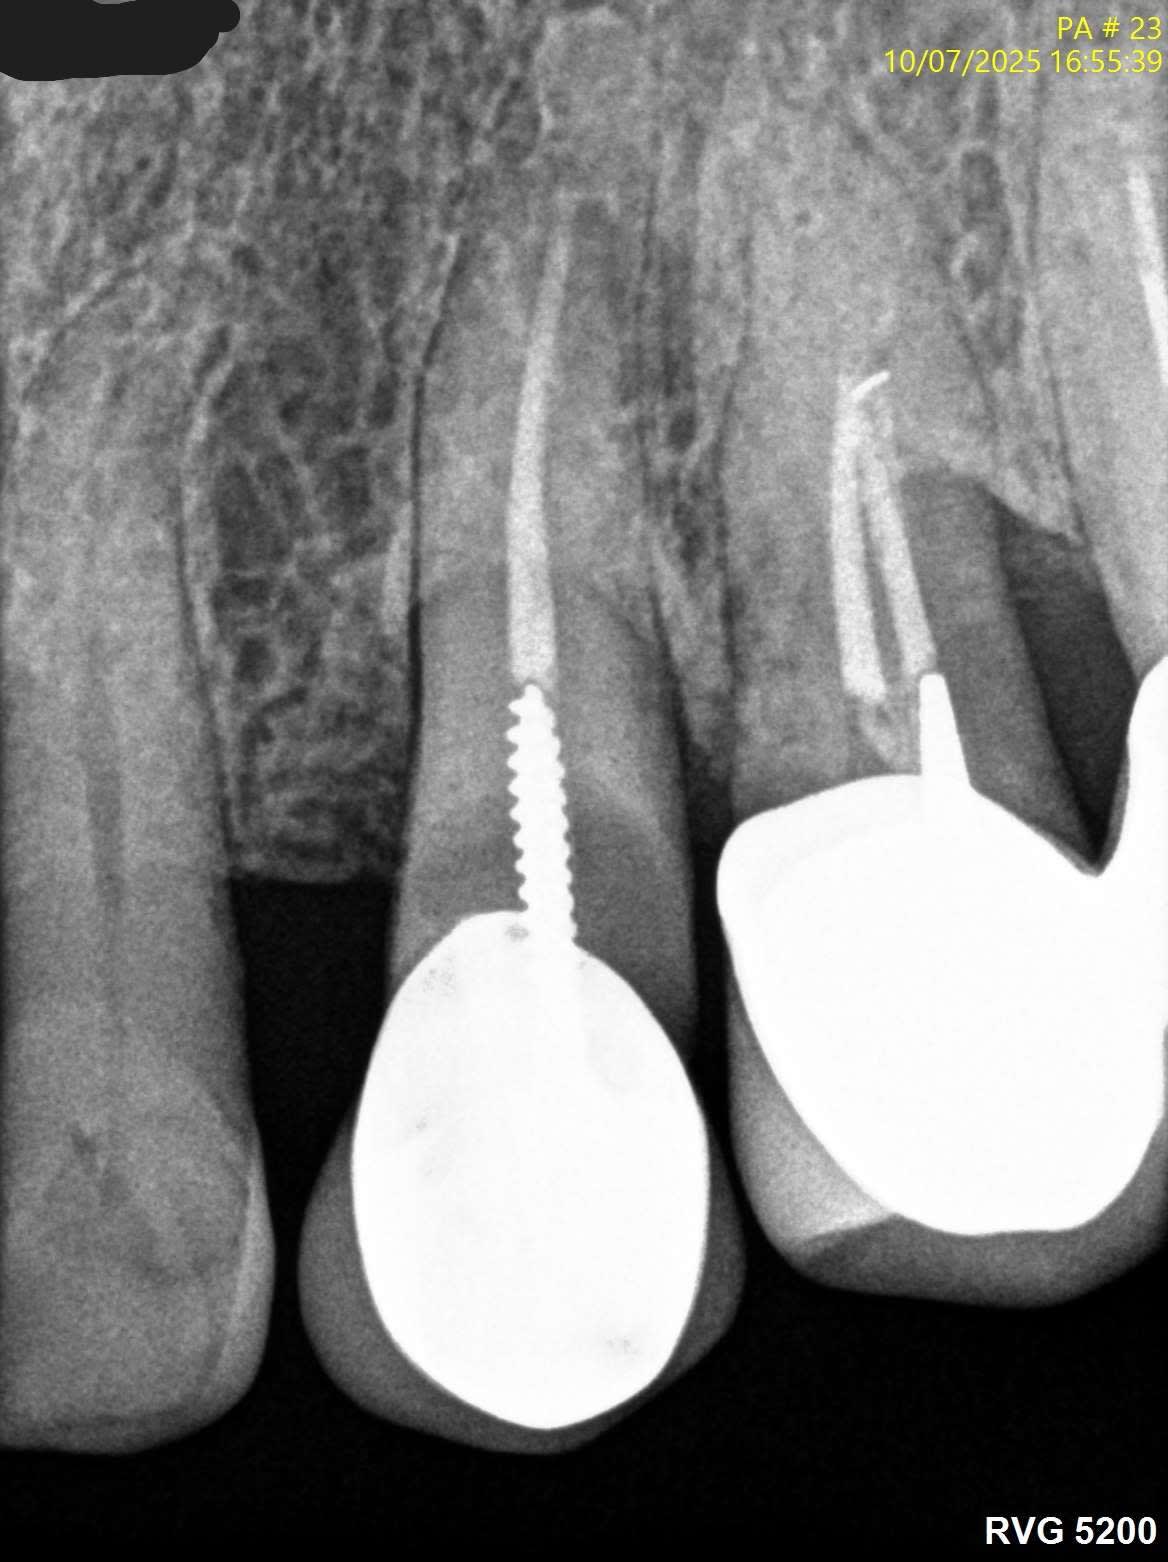

Sinon le screw post c est le top .

Les screw c'est top, ça tient jusqu'au bout xD

C'est quoi le souci c'est la limite composite dent ? Si c'est au sec aucun souci sinon les indications des composites seraient très limitées. Bon là c'est un cas extrême mais tu fais tes RCPE avec des matrices au sec, ton endo et ensuite restauration avec screw post pas de raison que ça se carie. Les inlay cores scellés dans le sang en one shot avec la couronne ça marche moyen aussi. Les composites foulés dans la salive ça marche pas ca marche pas non plus avec une vis.